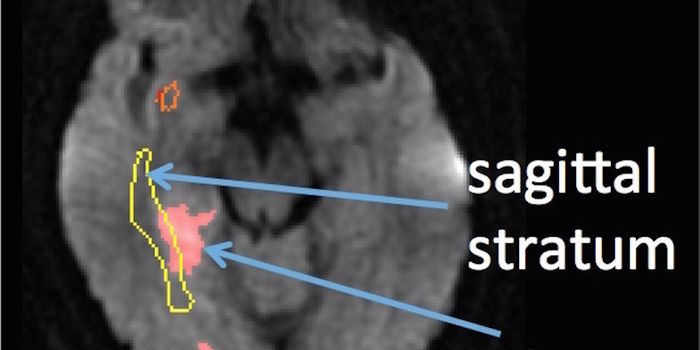

JUN 07, 2016NeuroscienceA traumatic brain injuries, or TBI, can be devastating and have long-lasting effects. In children these injuries can be ...